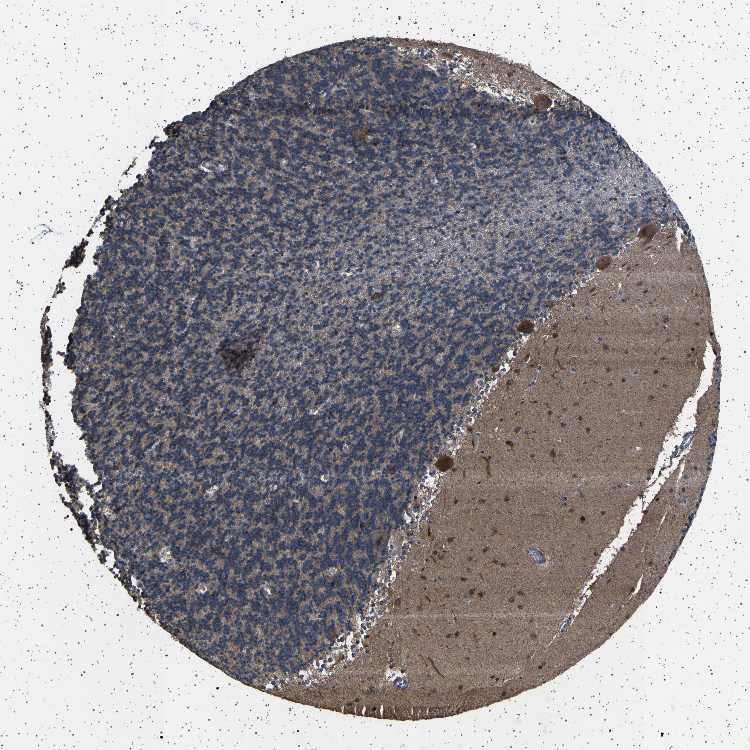

CEREBELLUM - Antibody stainingi

Antibody staining in the annotated cell types in the current human tissue is reported as not detected, low, medium, or high, based on conventional immunohistochemistry profiling in selected tissues. This score is based on the combination of the staining intensity and fraction of stained cells.

Each image is clickable and will lead to virtual microscopy that enables deeper exploration of all samples and also displays staining intensity scores, fraction scores and subcellular localization as well as patient and tissue information for each sample.

Antibody HPA020449

Purkinje cells High

Cells in granular layer Not detected

Cells in molecular layer High